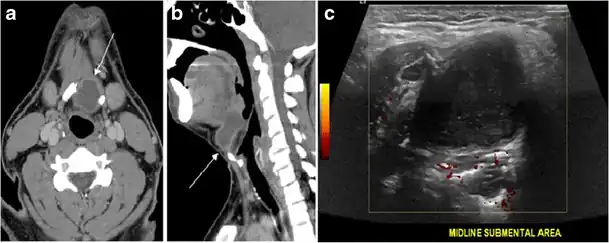

A thyroglossal duct cyst (TDC) is a duct remnant between the foramen cecum and thyroid isthmus. Most TDCs are located below the hyoid bone and in the midline. The more caudal the cyst, the more likely it will be off midline within 2 cm (Fig. 19 and and20).20). On a CT scan, a TDC appears as a well-circumscribed area of fluid attenuation with thin walls. The cyst wall can become thick with an enhancing rim indicative of current or previous infection. These cysts maybe complicated by haemorrhage, infection, or malignancy. Therefore, their US and CT scan appearance may vary based on their content. Nodular enhancement within a TDC should initiate further workup to exclude malignancy (Fig. 21). US-guided FNA of these suspicious nodular areas is considered an appropriate next diagnostic step, taking into consideration the high rate of false negative results.[1]